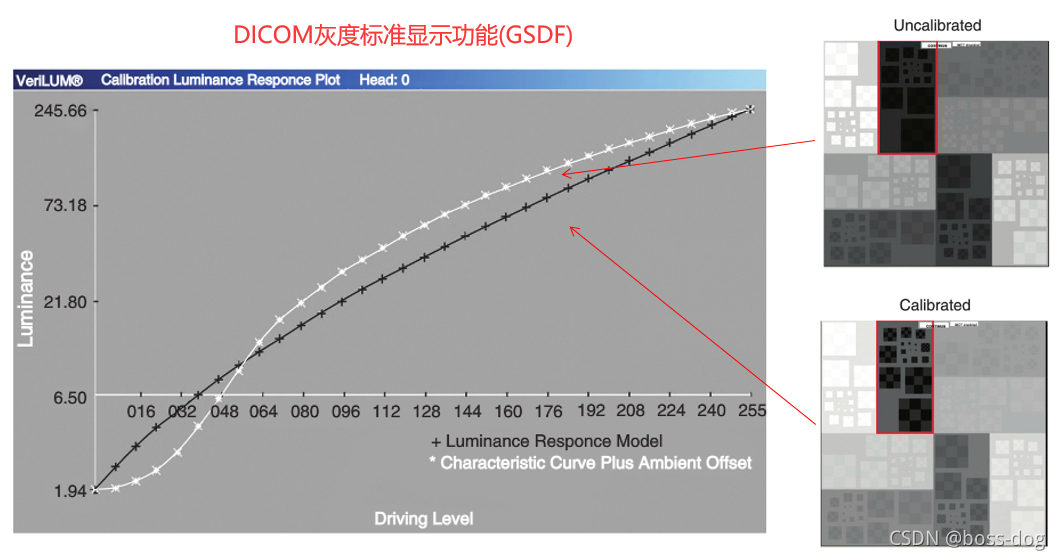

DICOM GSDF

显示器需要调,我们的显示器用的时间长了以后,它的颜色显示可能就会出现一个弱化,那么需要进行调节,将原始的图用黑白色在屏幕上面的亮暗进行最优的显示。

DICOM(医学数字影像和通讯)有个标准叫GSDF,用来把屏幕的显示进行优化校准,目前的显示器都有一键校准的功能。

上图的左边,黑颜色的线就是校准之后的,白颜色的线是校准之前不满足GSDF的曲线。

可以看到,未校准之前黑色的方块在灰色的方块中不那么明显,校准之后黑色的方块在灰色的方块中很明显,对比度增强了。